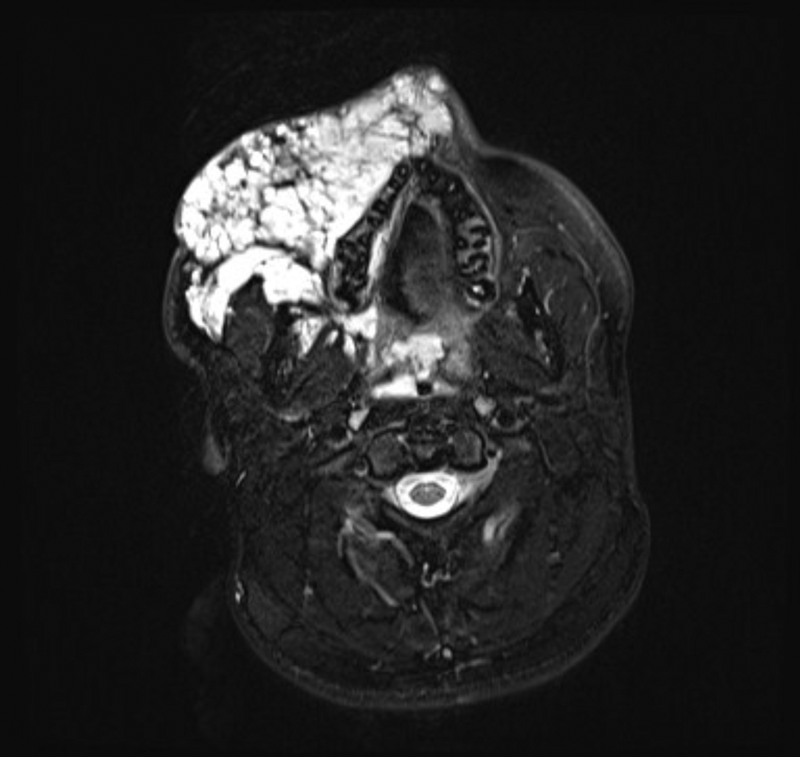

Figure 2: T2 weighted fat sat axial MRI image of extensive low-flow venous malformation

affecting the right side of the face and extending deep into the parapharangeal spaces.

The clinically evident portion of the lesion on examination is often only the minority of the mass volume and this is referred to as the ‘iceberg’, with the larger proportion of the lesion extending into the deeper anatomical spaces such as the parapharyngeal space, buccinator space and infra-temporal fossa [4]. This highlights the importance of a thorough imaging review to assess the full extent of the lesion and anatomical surroundings. Any treatment with sclerosants causes inflammation and swelling and this in turn can lead to compromise of adjacent structures, the most important being the airway. Imaging assessment typically consists of ultrasound and MRI. The sequences commonly used in a vascular anomalies protocol include T1 spin-echo sequences and T2 fat-saturated and / or short inversion recovery (STIR) imaging to delineate the lesion from the surrounding fat and determine its relation to surrounding structures, particularly the airway and neurovascular bundles. Post-contrast (gadolinium) MR imaging can be used but is not necessarily essential as a correct diagnosis can usually be made with clinical findings, site and the pre-contrast MR imaging [3, 5]. CT has little value in the assessment of low-flow lesions but can occasionally be of benefit if bones are involved.